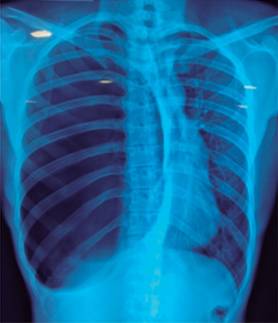

Paciente masculino de 38 años de edad, originario de la República de Kenia (África), de visita en México por cuestiones laborales. Acude a urgencias refiriendo que dos días previos a su ingreso, durante su viaje en avión desde Kenia y poco tiempo después de haber ingerido alimentos, inicia súbitamente con dolor abdominal opresivo a nivel del hipocondrio derecho, el cual se localizó para posteriormente irradiarse primero hacia la región dorsal y posteriormente hacia la cintura escapular ipsilateral en cuestión de minutos. Como fenómenos acompañantes refirió: cefalea, sensación de alza térmica sin cuantificación de la temperatura e hiporexia. Al interrogatorio dirigido negó: episodios de dolor similares en el pasado, ictericia, acolia, coluria, náusea, vómito, síntomas urinarios y/o alteración del hábito intestinal. Se automedicó con paracetamol, con mejoría parcial de la sintomatología. Acude a valoración con el personal médico del hotel que lo hospedaba, quienes tras examinarlo deciden referirlo a esta institución, con diagnóstico probable de colecistitis aguda. Como antecedentes de importancia destacan: tuberculosis pulmonar en 2002, múltiples cuadros de malaria y tabaquismo negado. El examen físico reveló signos vitales normales, caquexia, ruidos respiratorios disminuidos e hipertimpanismo a la percusión en el hemitórax derecho, choque de la punta cardiaca palpable en el quinto y sexto espacio intercostal izquierdo, con latido visible. Abdomen con dolor a la palpación en el hipocondrio derecho, con signo de Murphy (+), puño percusión costal derecho (+), Giordano derecho (+), timpanismo a la percusión, con peristalsis presente normoactiva, sin datos de irritación peritoneal. Los laboratorios no mostraron resultados relevantes. El ultrasonido de abdomen reportó: vesícula biliar adecuadamente distendida, con paredes delgadas regulares (longitud 6.25, grosor de 3.2 mm y diámetro transverso de 29 mm) y contenido completamente anecoico. La radiografía de tórax (Figura 1) mostró una estructura radiolúcida ovoidea que ocupaba aproximadamente 95% del hemitórax derecho, la cual ejercía efecto de masa desplazando el mediastino y el parénquima pulmonar izquierdo de la línea media hacia la izquierda, también se observó un desplazamiento caudal del hemidiafragma derecho y órganos intraabdominales por la estructura previamente descrita. La tomografía computarizada del tórax confirmó estos hallazgos compatibles con síndrome de pulmón evanescente, también conocido como enfisema bulloso gigante idiopático (Figura 2). Se solicitó interconsulta a cirugía de tórax. Por cuestiones personales, el paciente decide egresar de manera voluntaria de la sala de urgencias del hospital. Se coordina traslado al Servicio de Cirugía Torácica del Hospital General de México para ser intervenido quirúrgicamente, el paciente egresa hemodinámicamente estable y sin dolor.

No se encontraron en la literatura reportes sobre bullas gigantes que inicien con dolor abdominal como síntoma cardinal, como en el caso que nos ocupa. Los criterios radiográficos para el diagnóstico de síndrome de pulmón evanescente incluyen: bullas gigantes en uno o ambos lóbulos superiores que ocupan al menos 1/3 del hemitórax (30%) y comprimen el parénquima pulmonar normal circundante.7 La bullas gigantes a menudo simulan un neumotórax en apariencia radiográfica, lo cual puede conducir a errores diagnósticos y el manejo de las dos condiciones es muy diferente. La TAC de tórax es a veces necesaria para distinguir las bullas gigantes de un neumotórax. La tomografía computarizada de alta resolución es la mejor técnica de imagen para determinar con precisión la extensión y distribución de la enfermedad bullosa. El tratamiento suele ser quirúrgico y consiste en la resección de las bullas gigantes, especialmente en pacientes que presentan síntomas o desarrollan neumotórax espontáneo. Las opciones quirúrgicas incluyen toracotomía estándar y cirugía toracoscópica videoasistida, sin diferencias aparentes en los resultados entre un procedimiento y otro.8